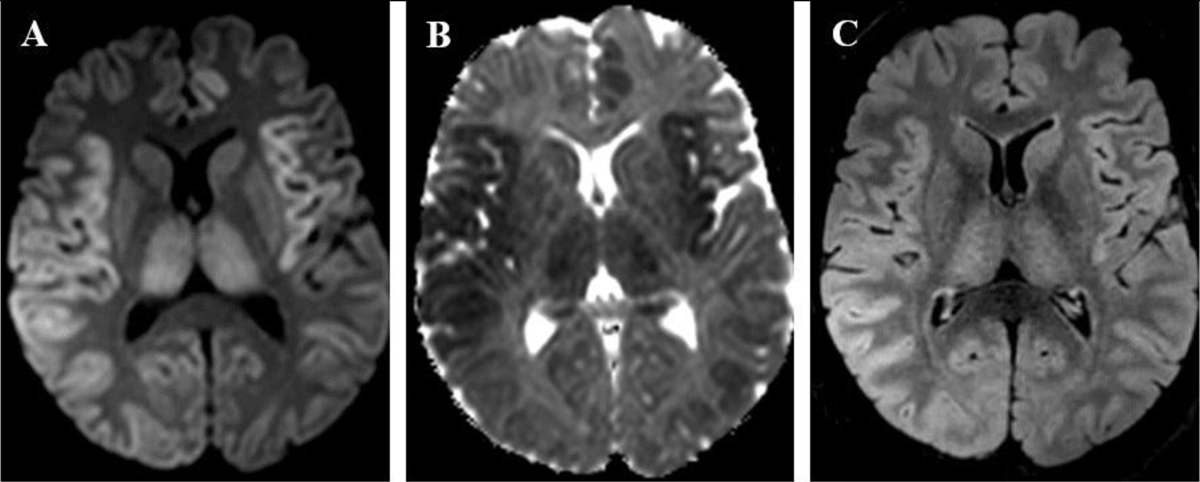

Figure 2

A 45-year-old man presented with seizures and fulminant hepatitis with hepatic failure, secondary to acetaminophen intoxication. (A) DWI (b-value = 1000 s/mm2) and (B) ADC map show cortical signal abnormalities in bilateral insulas and parietal lobes, left cingulate gyrus and both thalami, respectively high and low signal, consistent with cytotoxic edema. (C) FLAIR sequence shows high signal in the right parietal cortex and bilateral thalami.